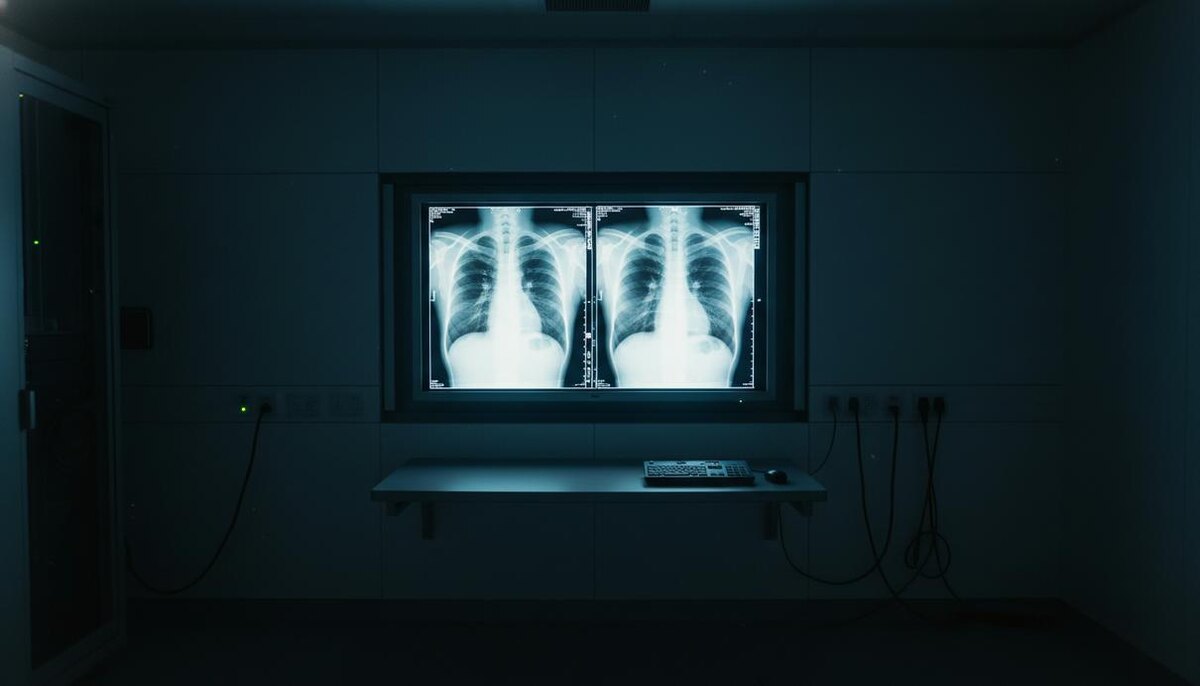

Исследование, опубликованное в журнале Radiology, показало, что опытные рентгенологи и современные мультимодальные языковые модели испытывают серьезные трудности с идентификацией медицинских изображений, созданных при помощи искусственного интеллекта. Специалисты не всегда могут отличить подлинные рентгенограммы от глубоких фейков, что ставит под угрозу безопасность цифровых архивов и достоверность диагностики.

В эксперименте приняли участие 17 врачей из 12 медицинских учреждений США, Франции, Германии, Турции, Великобритании и Объединенных Арабских Эмиратов. Профессиональный стаж участников варьировался от начинающих резидентов до экспертов с сорокалетним опытом. Специалисты из Школы медицины Айкана на горе Синай в Нью-Йорке подготовили для теста 264 снимка, половина из которых была синтезирована нейросетями.

Результаты проверки продемонстрировали, что бдительность врачей напрямую зависит от их информированности о возможных манипуляциях. Если рентгенологам не сообщали о наличии подделок в массиве данных, они успешно распознавали фальшивые снимки лишь в 41% случаев. После предупреждения о присутствии синтетического контента средняя точность идентификации выросла до 75%. При этом личные показатели медиков существенно разнились: точность определения изображений, созданных ChatGPT, колебалась в диапазоне от 58% до 92%.

Сами алгоритмы также оказались несовершенны в вопросах верификации контента. Модели GPT–4o, GPT–5, Gemini 2.5 Pro и Llama 4 Maverick показали точность от 57% до 85%. Примечательно, что даже GPT–4o, использованная для генерации части снимков, не смогла выявить все собственные имитации, хотя и справилась лучше конкурентов. При оценке рентгенограмм грудной клетки, созданных моделью RoentGen от Стэнфордского университета, точность искусственного интеллекта составила от 52% до 89%, в то время как показатели врачей находились в пределах 62–78%.

Авторы работы подчеркивают, что многолетний стаж не гарантирует успеха в поиске подделок – некоторое преимущество имели лишь узкие специалисты в области скелетно-мышечной радиологии. Основными признаками фальсификации оказались избыточная четкость и симметрия. На синтетических снимках кости выглядят слишком гладкими, позвоночник – неестественно прямым, а легочный рисунок и сосудистая сетка – чрезмерно однородными. Переломы на таких изображениях часто выглядят слишком «чистыми» и локализованными на одной стороне кости.